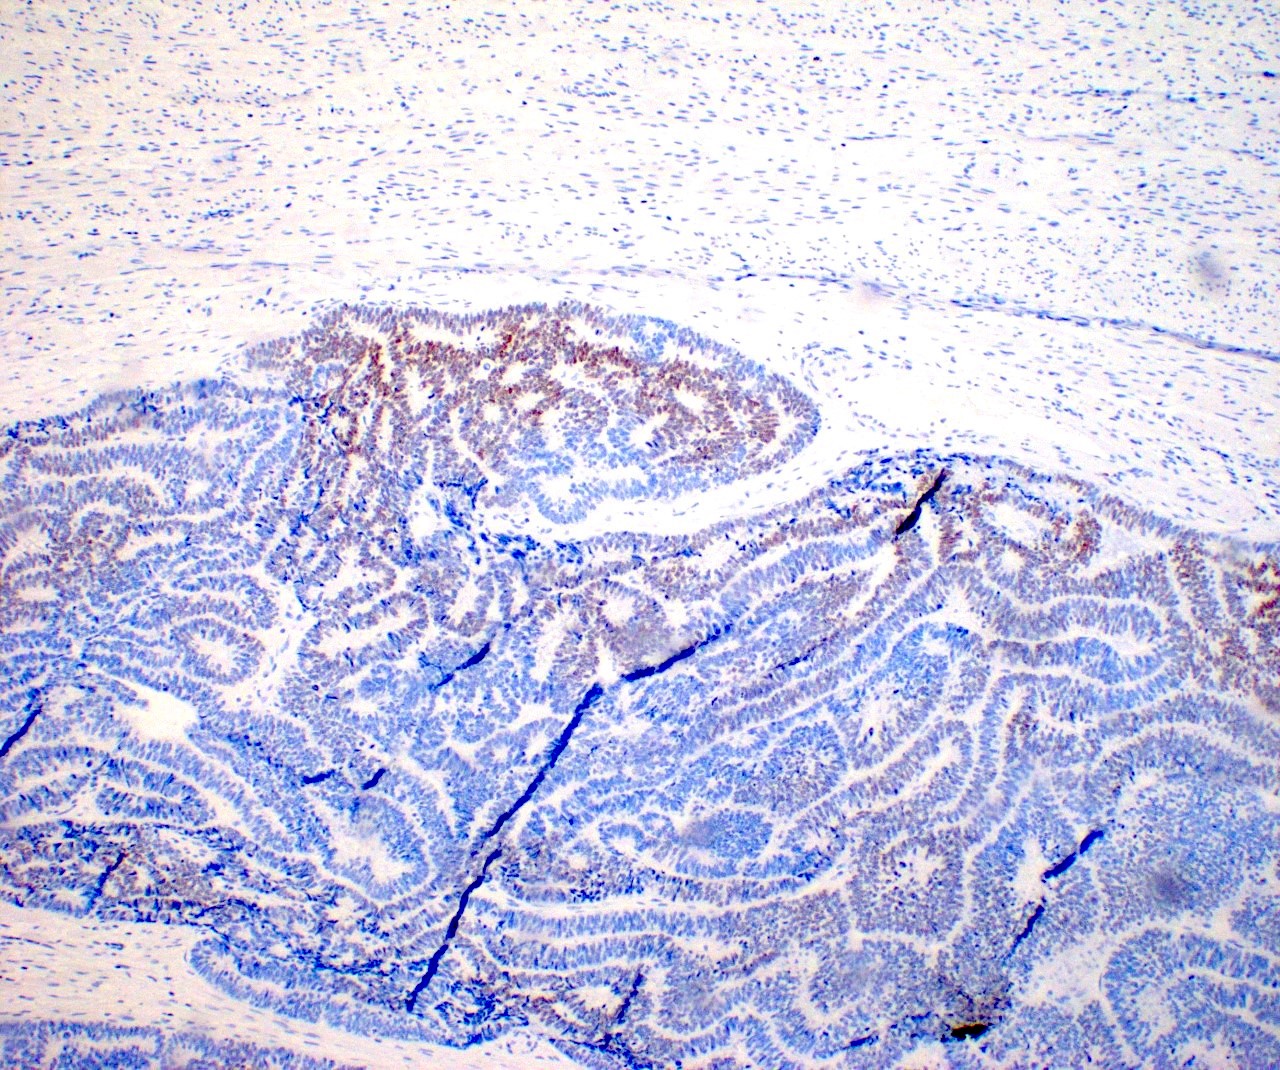

Microscopic (histologic) images

Contributed by Daniel Graham, M.D., Adele Wong, M.B., B.Ch., B.A.O. and Lucy Ma, M.D.

Negative stains

- ER

- PR (more reliable negative marker than ER)

- Calretinin (usually negative may be focally positive)

- Reference: J Clin Med 2021;10:698